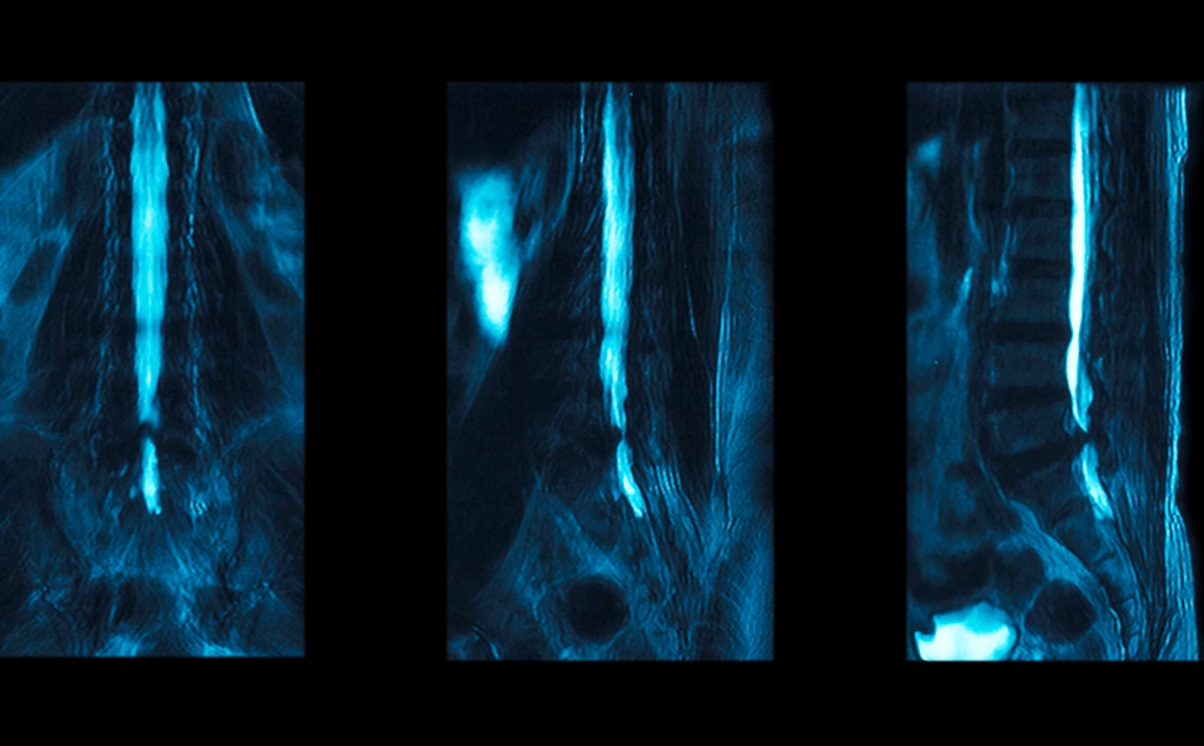

LJ had an MRI scan a week later and was advised that this showed a haematoma, probably caused by the administration of the spinal block, but this would heal.

In November 2013, LJ received a letter from her anaesthetist suggesting that the MRI scan from August in fact showed damage to the lower end of her spinal cord and the spinal block was the likely cause. She met the anaesthetist who was apologetic but did not suggest that the damage was permanent.